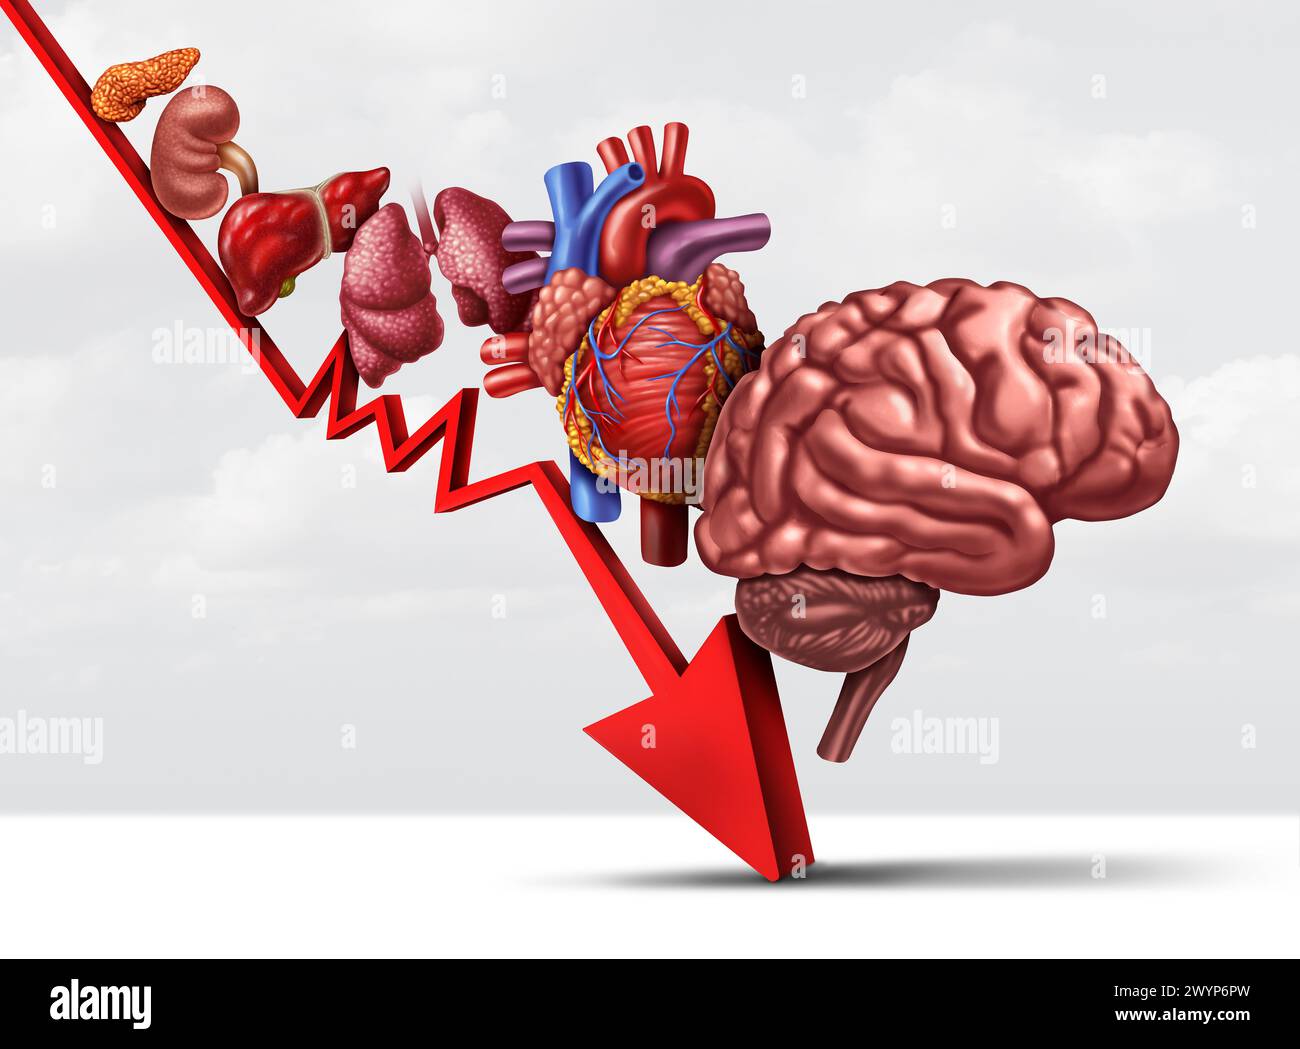

Declining Human Health and aging process of organs as decreasing functioning of the heart lungs kidney pancreas and brain as a healthcare or health-ca Stock Photohttps://www.alamy.com/image-license-details/?v=1https://www.alamy.com/declining-human-health-and-aging-process-of-organs-as-decreasing-functioning-of-the-heart-lungs-kidney-pancreas-and-brain-as-a-healthcare-or-health-ca-image602236513.html

Declining Human Health and aging process of organs as decreasing functioning of the heart lungs kidney pancreas and brain as a healthcare or health-ca Stock Photohttps://www.alamy.com/image-license-details/?v=1https://www.alamy.com/declining-human-health-and-aging-process-of-organs-as-decreasing-functioning-of-the-heart-lungs-kidney-pancreas-and-brain-as-a-healthcare-or-health-ca-image602236513.htmlRF2WYP6PW–Declining Human Health and aging process of organs as decreasing functioning of the heart lungs kidney pancreas and brain as a healthcare or health-ca